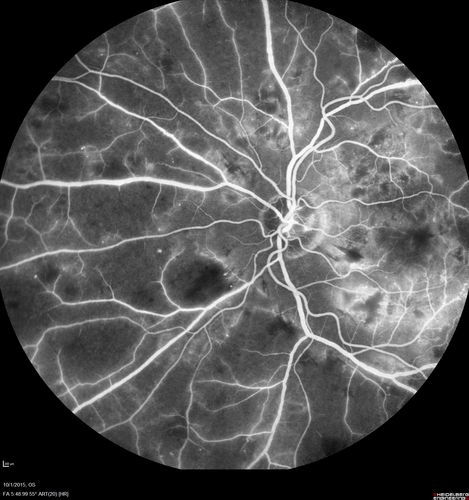

Hairy Cell Leukemia - Retinal Hemorrhage and twig Branch Vein Occlusion

79 year old man He has had hairy cell leukemia since 2002.  He is in remission.  His last blood tests were 9/2018.  He just moved down here and needs a new leukemia doctor.  His vision is fine.

VA OD: Dcc20/25

VA OS: Dcc20/25

IOP: TP: OD:12 OS:12